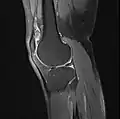

MRI

Both anterior cruciate ligament (ACL) and posterior cruciate ligaments (PCL) are hypointense on both T1 and T2 weighted images of MRI. However, some high signal striations are often seen at the distal part of the ACL, making ACL higher intensity than PCL on MRI scans.[17]

Knee MRI (PD TSE FS sagittal)